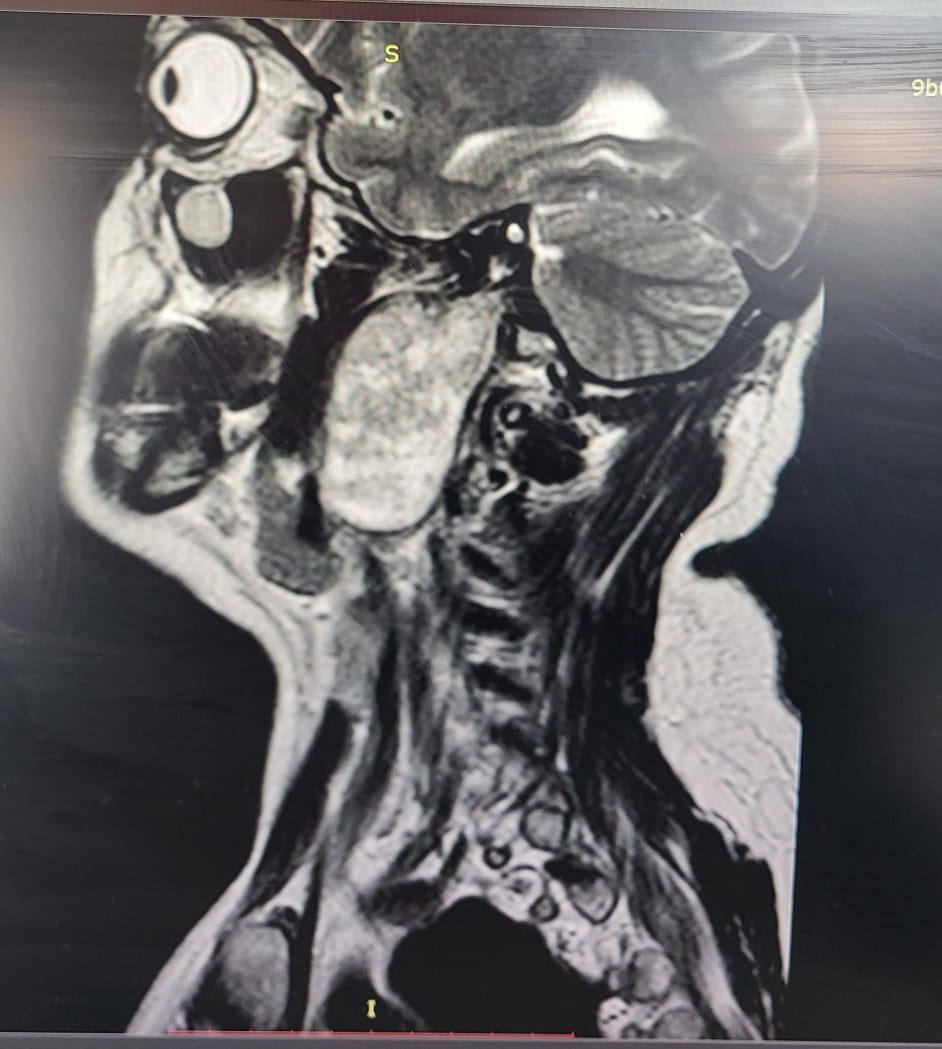

Женщина жаловалась на заложенность уха и увеличение небной миндалины. Результаты исследований выявили у нее в голове объемное образование. Это оказалась шваннома – доброкачественная опухоль, которая развивается из оболочек нервных клеток.